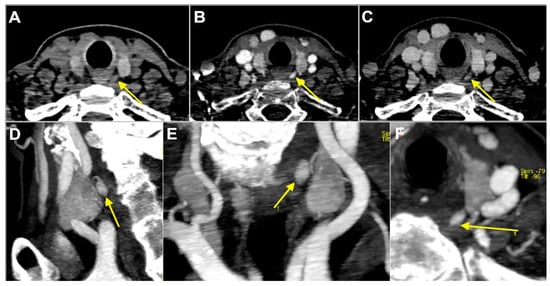

Figure 4. Enlarged left superior parathyroid in 53-year-old woman with primary hyperparathyroidism. Yellow arrow indicates 9 mm soft tissue nodule located posteriorly to third medium of left thyroid lobe, hypodense to thyroid parenchyma on non-contrast-enhanced phase (A), hyper enhancing on arterial phase (B) with subsequent wash-out on delayed phase (C). Reformatted sagittal (D), coronal (E), and axial (F) maximum intensity projection images obtained by arterial phase scan demonstrate upper enlarged polar vessel.